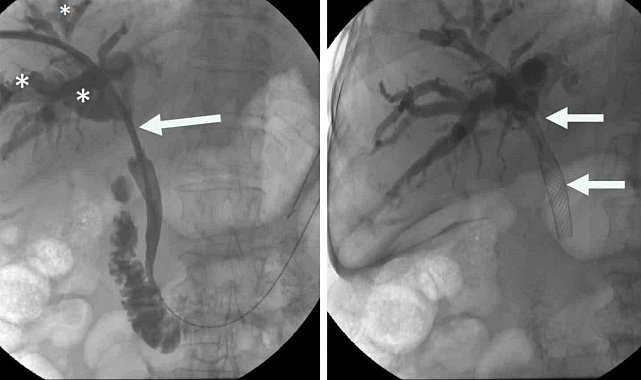

İzmir Ekonomi Üniversitesi Medical Point Hastanesi Tıbbi Direktör Ahmet Memiş'in öncülüğünde, farklı tıp disiplinlerinin işbirliğiyle geliştirilen hibrit yaklaşımlar, endoskopik, gastro ve girişimsel radyoloji teknikleri bir araya getirerek karmaşık safra yolu sorunlarında çığır açıyor. Bu yenilikçi yöntemler, hastaların iyileşme süreçlerini hızlandırırken, daha az travmatik operasyonlarla tedavi imkanı sunuyor.Prof. Dr. Ahmet Memiş'in önderliğinde uygulanan bu yenilikçi yöntem, endoskopik teknikleri ve iğne ile giriş yöntemlerini tek bir operasyonda birleştiriyor. Bu sayede, daha önce tedavisi çok zorlu kabul edilen karmaşık safra yolu problemleri artık daha etkili ve minimal invaziv bir şekilde tedavi edilebiliyor. Hibrit yaklaşımların en önemli avantajlarından biri, hastaların bedenine minimum düzeyde zarar vermesidir. Büyük cerrahi kesilerin yerine, endoskopik, gastro ve girişimsel radyoloji yöntemler kullanılarak, iğne deliği kadar küçük girişimlerle operasyonlar gerçekleştiriliyor. Bu da hastaların ameliyat sonrası ağrılarını azaltıyor, enfeksiyon riskini düşürüyor ve hastanede kalış sürelerini kısaltıyor.'Hibrit yaklaşım'Prof. Dr. Ahmet Memiş, "Hibrit yaklaşım, sadece tedavi değil, aynı zamanda tanı sürecinde de önemli avantajlar sunuyor. Hekim, hastanın vücuduna dokunmadan, radyolojik görüntüleme teknikleriyle hastalıklar daha hızlı ve doğru bir şekilde tespit ediliyor. Bu da tedavi sürecinin daha etkin bir şekilde planlanmasına imkan sağlıyor. Farklı disiplinlerden uzman hekimlerin bir araya gelerek oluşturduğu sinerji, karmaşık safra yolu sorunlarında başarı oranını önemli ölçüde artırıyor. Bu sayede, hastalar daha hızlı iyileşme göstererek günlük yaşamlarına daha kısa sürede dönebiliyor. Geleneksel cerrahi yöntemlerde uzun iyileşme süreleri ve yoğun ağrılar yaşanırken, minimal invaziv yaklaşımlar sayesinde bu sorunlar ortadan kalkıyor. Hastalar, operasyon sonrası çok daha kısa sürede taburcu oluyor ve gündelik aktivitelerine hızla dönebiliyorlar. Bu da hem hasta konforunu artırıyor hem de sağlık sisteminin üzerindeki yükü hafifletiyor" dedi.Memiş, "Radyologlar, gastroenterologlar ve cerrahlar gibi farklı uzmanlık alanlarından hekimlerin bir araya gelerek oluşturduğu sinerji, daha önce çözümsüz görünen pek çok sağlık sorununa yenilikçi çözümler sunuyor. Bu durum, tıp dünyasında disiplinlerarası işbirliğinin önemini bir kez daha gözler önüne seriyor" diye konuştu.

İzmir Ekonomi Üniversitesi Medical Point Hastanesi Tıbbi Direktör Ahmet Memiş'in öncülüğünde, farklı tıp disiplinlerinin işbirliğiyle geliştirilen hibrit yaklaşımlar, endoskopik, gastro ve girişimsel radyoloji teknikleri bir araya getirerek karmaşık safra yolu sorunlarında çığır açıyor. Bu yenilikçi yöntemler, hastaların iyileşme süreçlerini hızlandırırken, daha az travmatik operasyonlarla tedavi imkanı sunuyor.